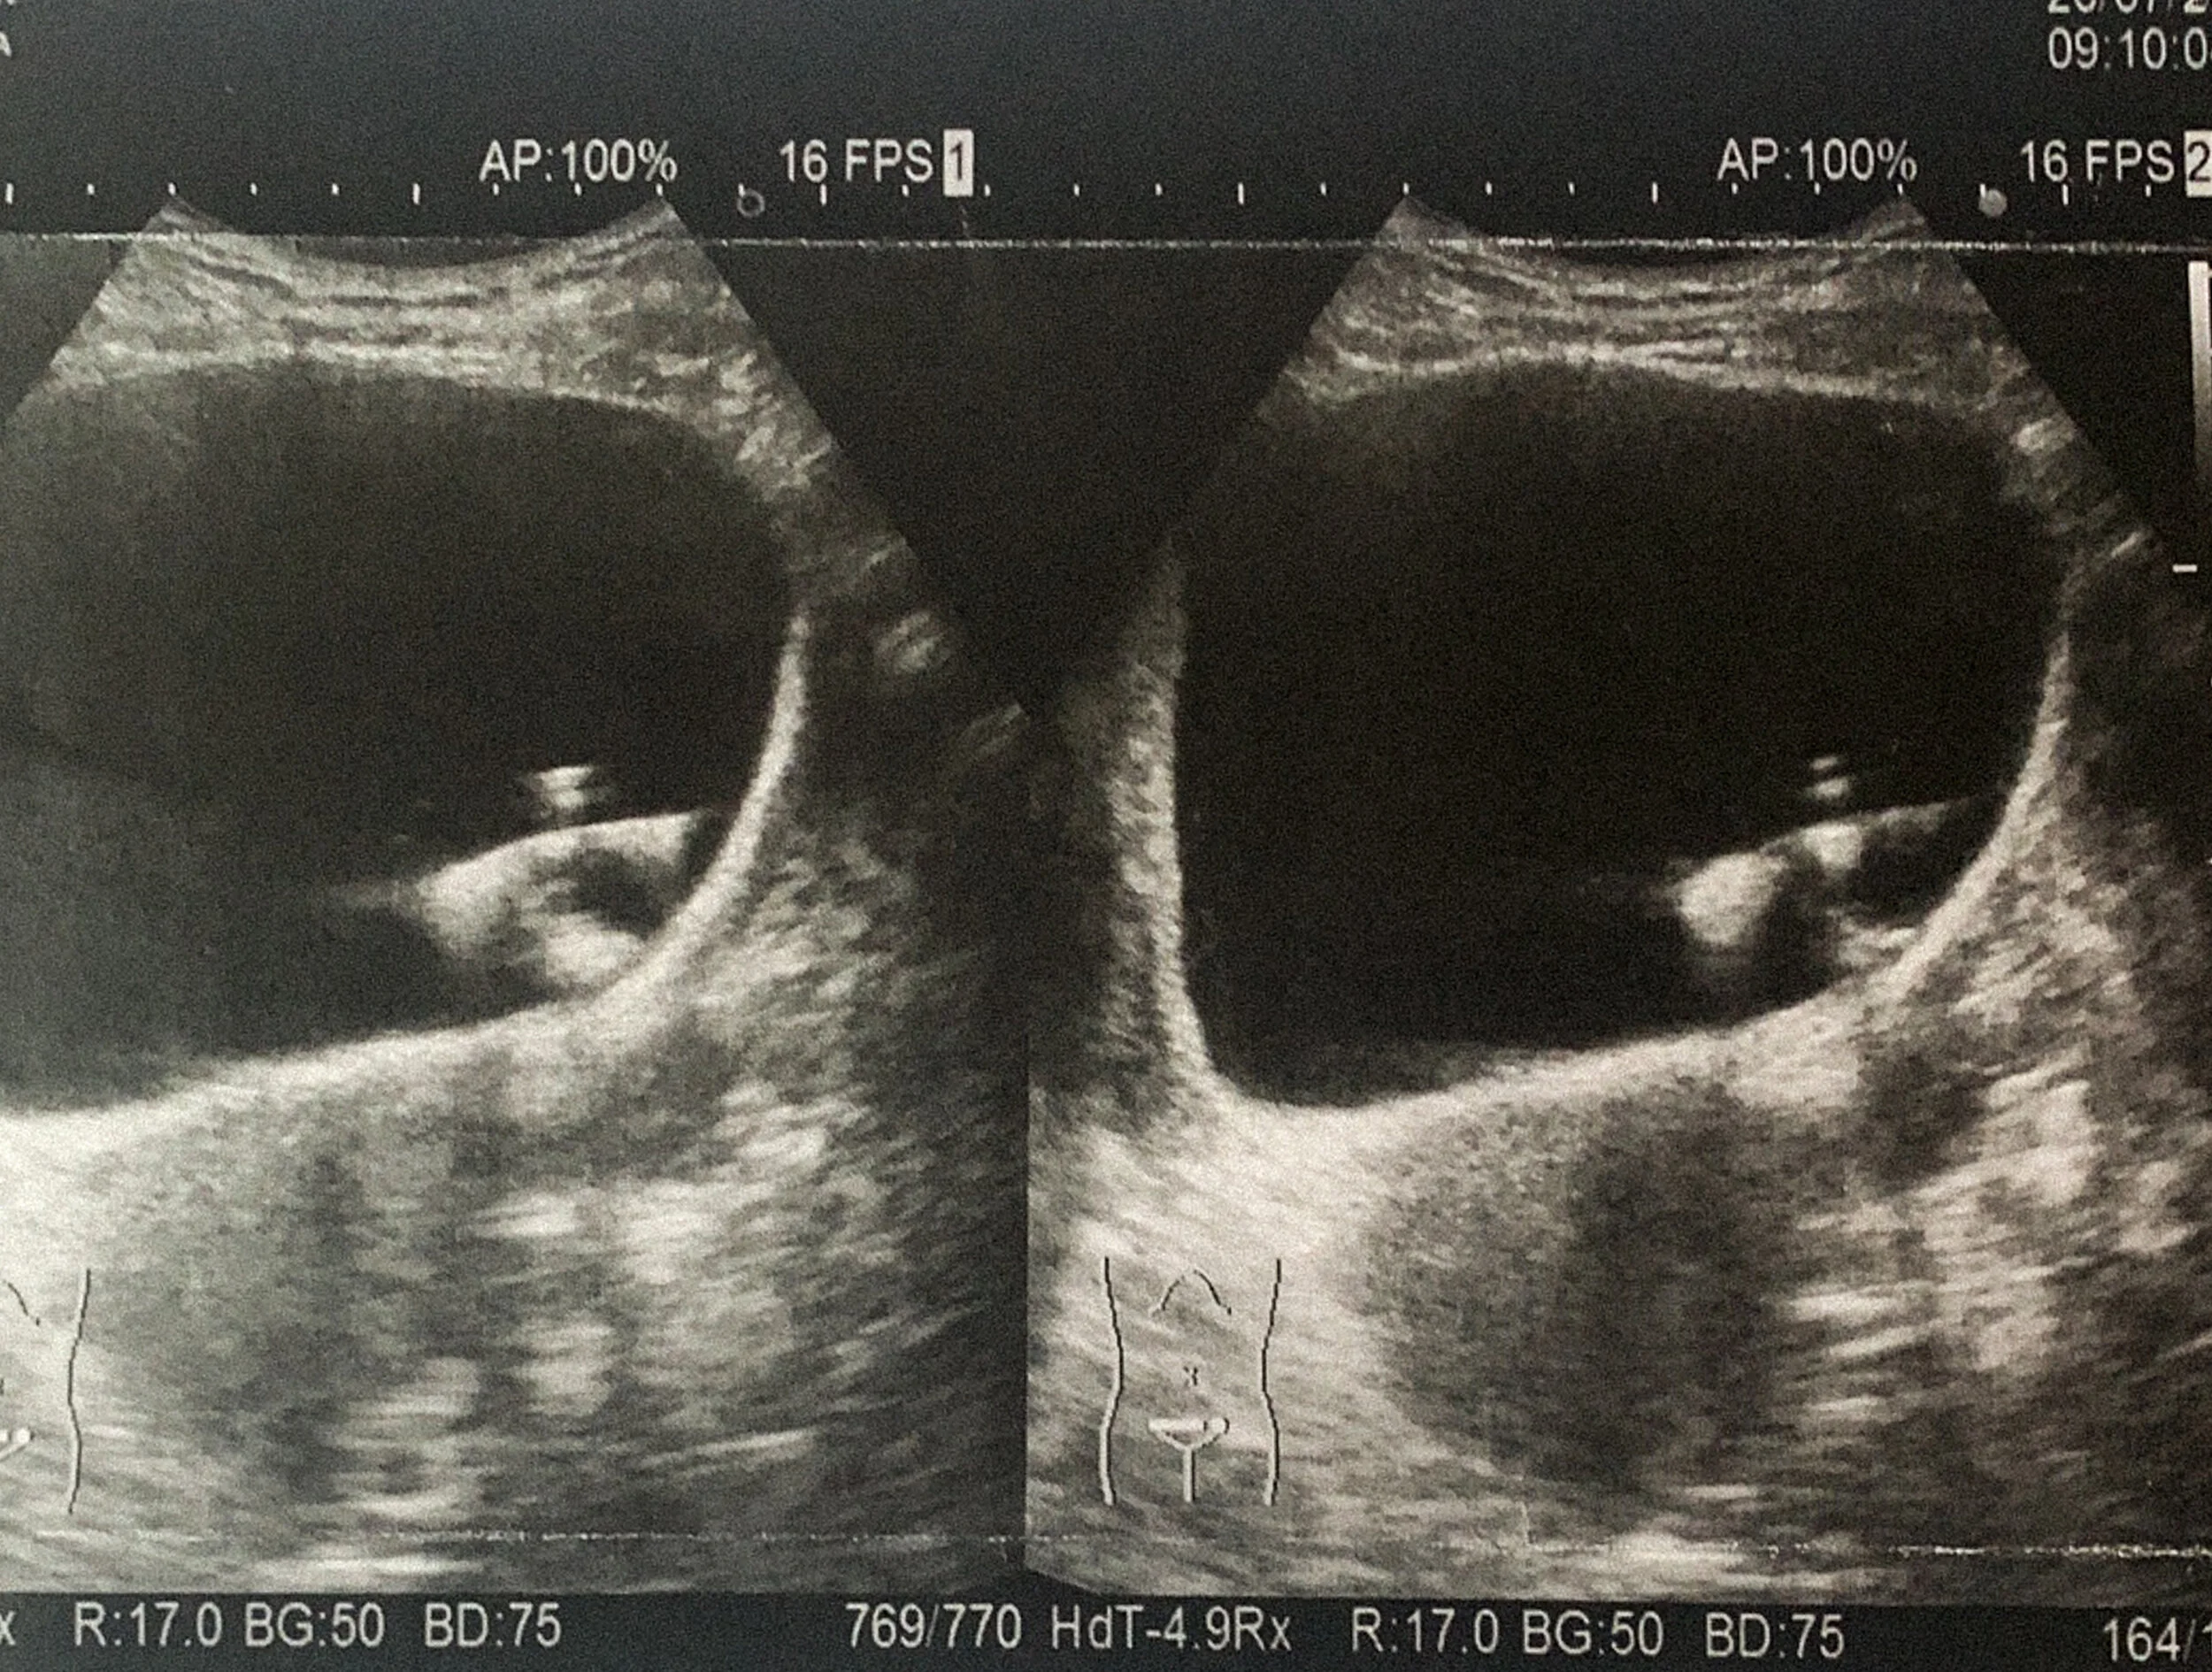

My appointment day arrives- I met a translator who escorted me to the hospital. My visit went quickly- No exam room really, you are directed to a desk behind a curtain in the lobby, discuss your problems through the translator, and are told to sit in the waiting room again. I did gather that it would be a trans-vaginal ultrasound, then prepped by my sweet translator of what that entails here in Japan… Holy wow. Very different then the states friends!!!! I was escorted to a tiny closet space, with a very scary exam chair- think flesh colored Dental seat with a hole cut out in the bottom, metal bucket underneath… They gave me a washcloth to cover up with, and said “ just sit still, the chair will do the rest.” WHAT??? It automatically turned, laid me back, and spread my legs under a curtain behind me- Hello Doc! (And everyone else I could hear walking and talking behind that stained sheet!) So damn uncomfortable. Exam only took like 2 minutes tho, and bottom line, NO PROLAPSE. (Lots of painful pelvic floor Yoga to waste!) Enlarged uterus was detected and she saw something in my bladder. Told me that a hysterectomy would be wise with my endometriosis, but that I needed to see a Urologist, and Soon. Went home. Cried the whole way.

I had my next appointment with my new PCM within a week. He went over EVERYTHING with me. He explained my labs and levels, which hadnt been done at all to this point, looked at my ultrasound photo from GYN and said it was a possible foreign object. Thats impossible tho…. So im thinking the worse. He gave me personal contact info for him. Then he confirmed my appointment with urology and calmed me down. He told me not to think Cancer- its rare, im young, no way. I honestly felt like I could breathe again, at least for a minute. Thats all it takes, someone on your side. A fellow advocate for your Health.

Urology is in another hospital, and its nicer. Im pacing the lobby, watching Flood coverage on the Japanese news, and holding my pee. You have no idea how painful this is. Im physically shaking in pain. But have to have a full bladder for the ultrasound. The nurses see how bad off I am and get me in asap. The doc takes a look, belly US, and sees something large. He says something in Japanese I dont understand and I bolt to the restroom. In the hall, my translator holds my hands and tells me he needs to do a scope to see what is going on, he found something. She looks concerned, yet tells me its all going to be Ok. I wait an hour.

The translator is with me, talking me through every step. I undress, lay down on the table, and get pink bunny long socks placed to keep me warm. Japan. Then wait about 15 mins for the Doc. They are playing amusement park music softly in the room. Japan. Its not that bad so far, But I still cant breathe. he comes in and explains the procedure (with arm gestures and my translator explaining the best she can)- scope tube thingy with light and camera up the urethra- Honestly im in so much pain, I hardly feel it. Upon insertion, he grabs the computer screen on the rotating arm from behind my head and says in broken English “SEE! Foreign object!” Banging his finger on the screen. And I took a breath. I dont have cancer. I dont know what the hell it is, it looks like a battleship in the bottom of the Ocean. Metal and white and tarnished. My mind fills with C section surgeries Iv had, did they leave something in me?? I dont have time to contemplate, its not CANCER. I let out a sob and say “Ok, when do I schedule a surgery to remove it??” He says “Ichi, Ni, San” (1,2,3) and rips it out. Through my Urethra. No warning. I scream and literally levitate off of the table. They heard me in the waiting room. He holds up his hand with the scope in it, and says “Stint!” Eyes wide a saucers.

Nope. IUD.

And we still arent done. I immediately feel relief in my stomach and bladder. But there is more. There are two long pieces of metal, and he cant get them with this scope. He needs the bigger one. Ok. Yey. lets do this.

Nurses bring me back and prep me for the next cystoscopy, this room is high tech and no joke. My translator is freaking out, keeps telling me how brave I am, how am I doing this??? Yeah, no pain meds in Japan for this kind of thing, but I couldnt have cared less, you could have ripped off my arm, I am going to be fine!!!! Bunny socks. Dimmer lights. This scope was bigger, and I defiantly felt it. My urethra tube was inflamed- raw. There were two 1.5” wires woven through my bladder wall. Each one, “Ichi, Ni, San” Deep breathe and RIP! We got it all out.

The Urologist had never seen anything like this before, ever. I explained it was my IUD, planted 9 years ago, which I was told was expelled weeks post insertion. Um nope. It had worked its way up through my uterus, growing through my uterine and bladder wall. The infections I was suffering from had become completely immune to all antibiotics, they had adhered to the IUD itself. I was told I was lucky, I could have a hole in my bladder, which he checked again for, I could have gone septic from the infections. He was surprised I was standing there. I was prescribed another round of Levo to kill off anything left, informed about and how to watch for Sepsis, and told to come back in a month so he could check up on me… We bowed, I cried and thanked him so so so much, and he sent on my way.